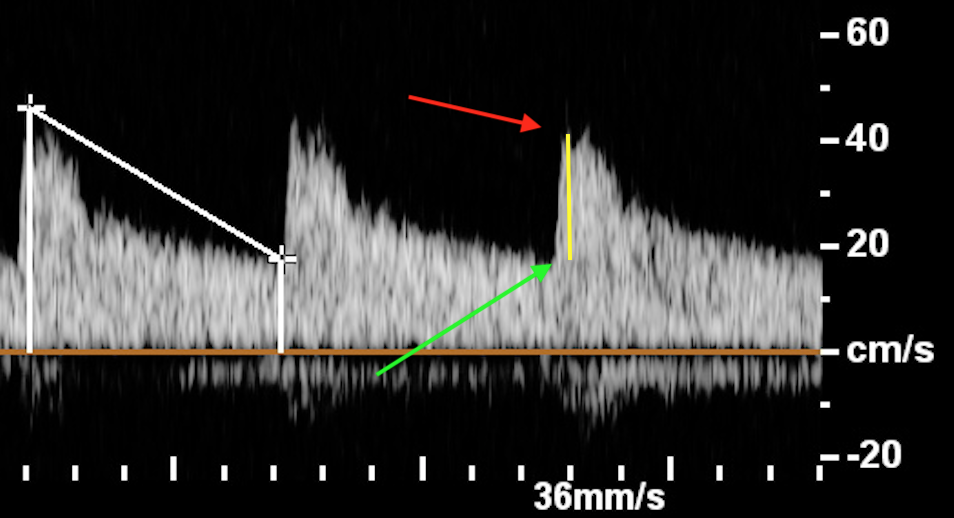

You need to check and make sure the “t” markers (as seen on first sequence in this photo) are at the top (red arrow) and bottom (green arrow) otherwise you will get wrong values.

The yellow line is the acceleration velocity and should be almost a straight line normally.

Waveform seen in arterial stenosis, including RAS.

There is a stenosis so it takes longer to reach the peak velocity as there is a huge roadblock.

It also takes longer to get back to baseline values simply because there is less flow overall.